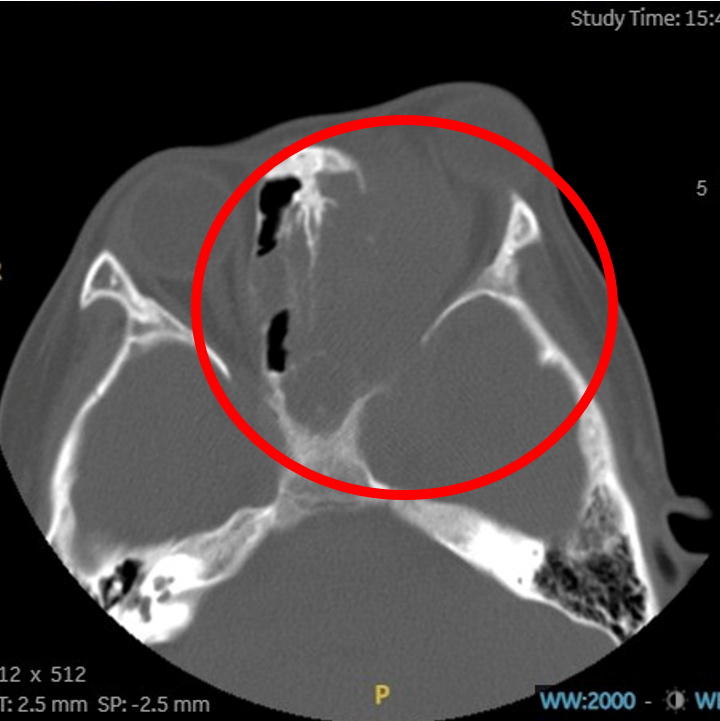

2023年底,青大附院西海岸院区儿童血液肿瘤科接诊了一名“特殊”的患儿,患儿左侧眼球突出明显,无法闭合,眼部周围组织糜烂肿胀,附有大量黄绿色分泌物,接下来的检查结果更让所有人倒吸一口凉气——影像学检查显示,患儿左侧筛窦、上颌窦、蝶窦、眼眶及鼻道内存在一巨大占位,大小约48mm×60mm×56mm的肿瘤,且已突破解剖屏障,向上侵入颅前中窝、海绵窦,向后包绕左侧颈内动脉,并严重压迫左侧视神经。病理活检最终明确为横纹肌肉瘤。

停药后影像学复查